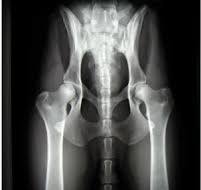

Les Dysplasies